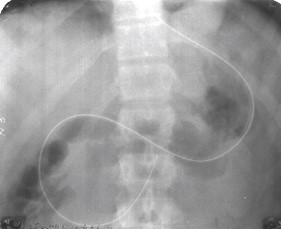

- Острая кишечная непроходимость. Это критическое состояние, требующее немедленной госпитализации в хирургический стационар. На рентгенограммах можно увидеть перерастянутые газом кишечные петли с горизонтальными уровнями жидкости, известные как чаши Клойбера.

При тонкокишечной непроходимости длина чаши превышает ее высоту. В случае, если препятствие находится в толстой кишке, наблюдается обратная картина — высота газового пузыря больше ширины уровня жидкости.

Необходимо различать механическую и динамическую непроходимость для выбора дальнейшей стратегии лечения (консервативной или хирургической). При механической непроходимости кишечные петли выше места предполагаемого патологического процесса значительно расширены, тогда как дистальнее они сужаются. Уровни жидкости располагаются на разных высотах, и их местоположение меняется из-за усиленной перистальтики.

Динамическая непроходимость характеризуется стабильной рентгенологической картиной.